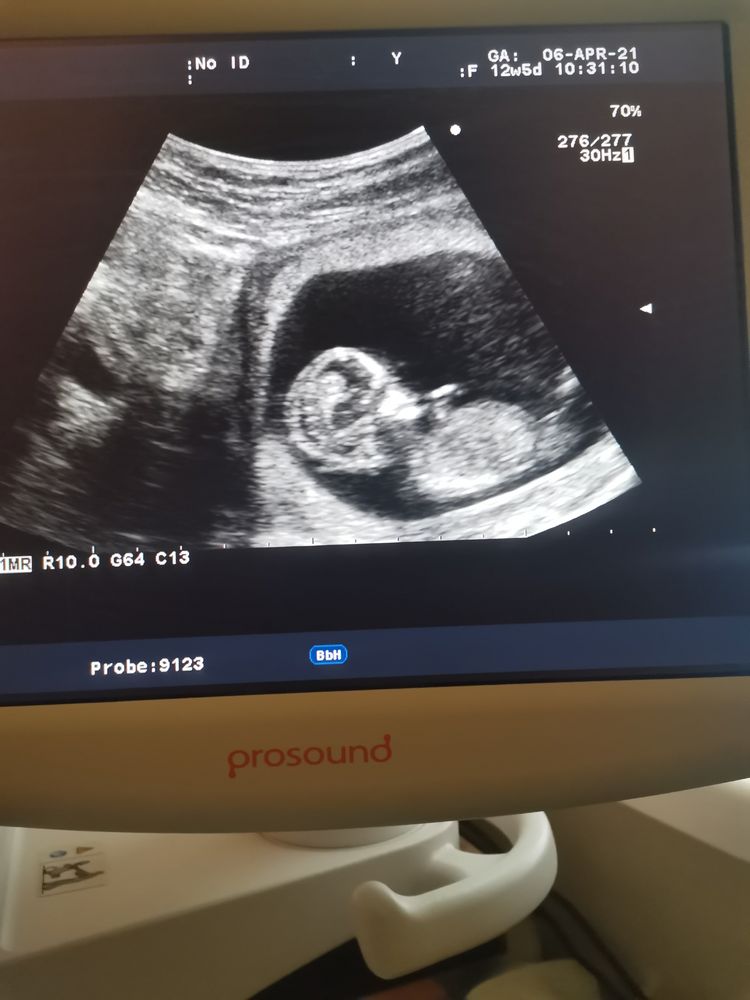

жду мальчика, 17 неделя

1 скрининг

Врач сказал, что по узи все хорошо. Разрешила сфоткать экран. Потом разглядывала фото и поняла, что носа, да и вообще профиль я не вижу. В описании указано, носовая кость - 2мм. Может просто неудачный ракурс?

А в самом процессе показывали экран? Я четко и нос и уши разглядела у своего, а когда на телефон сфотографировала, тоже получилось размыто. Носовая кость 2,3 мм, сказали что норма, так что не переживайте)